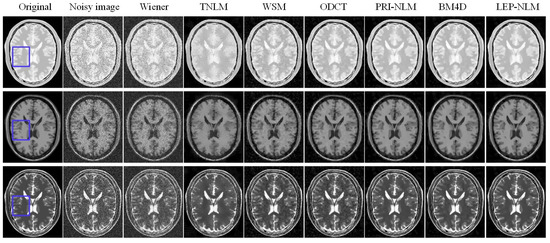

3.1. Simulated MR Images